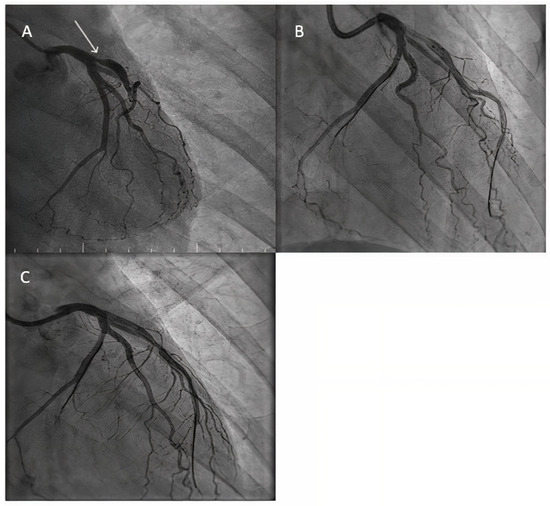

- Uskela, S.; Eranti, A.; Kärkkäinen, J.M.; Rissanen, T.T. Drug-coated balloon-only strategy for percutaneous coronary intervention of de novo left main coronary artery disease: The importance of proper lesion preparation. Front. Med. 2023, 17, 75–84. [Google Scholar] [CrossRef]